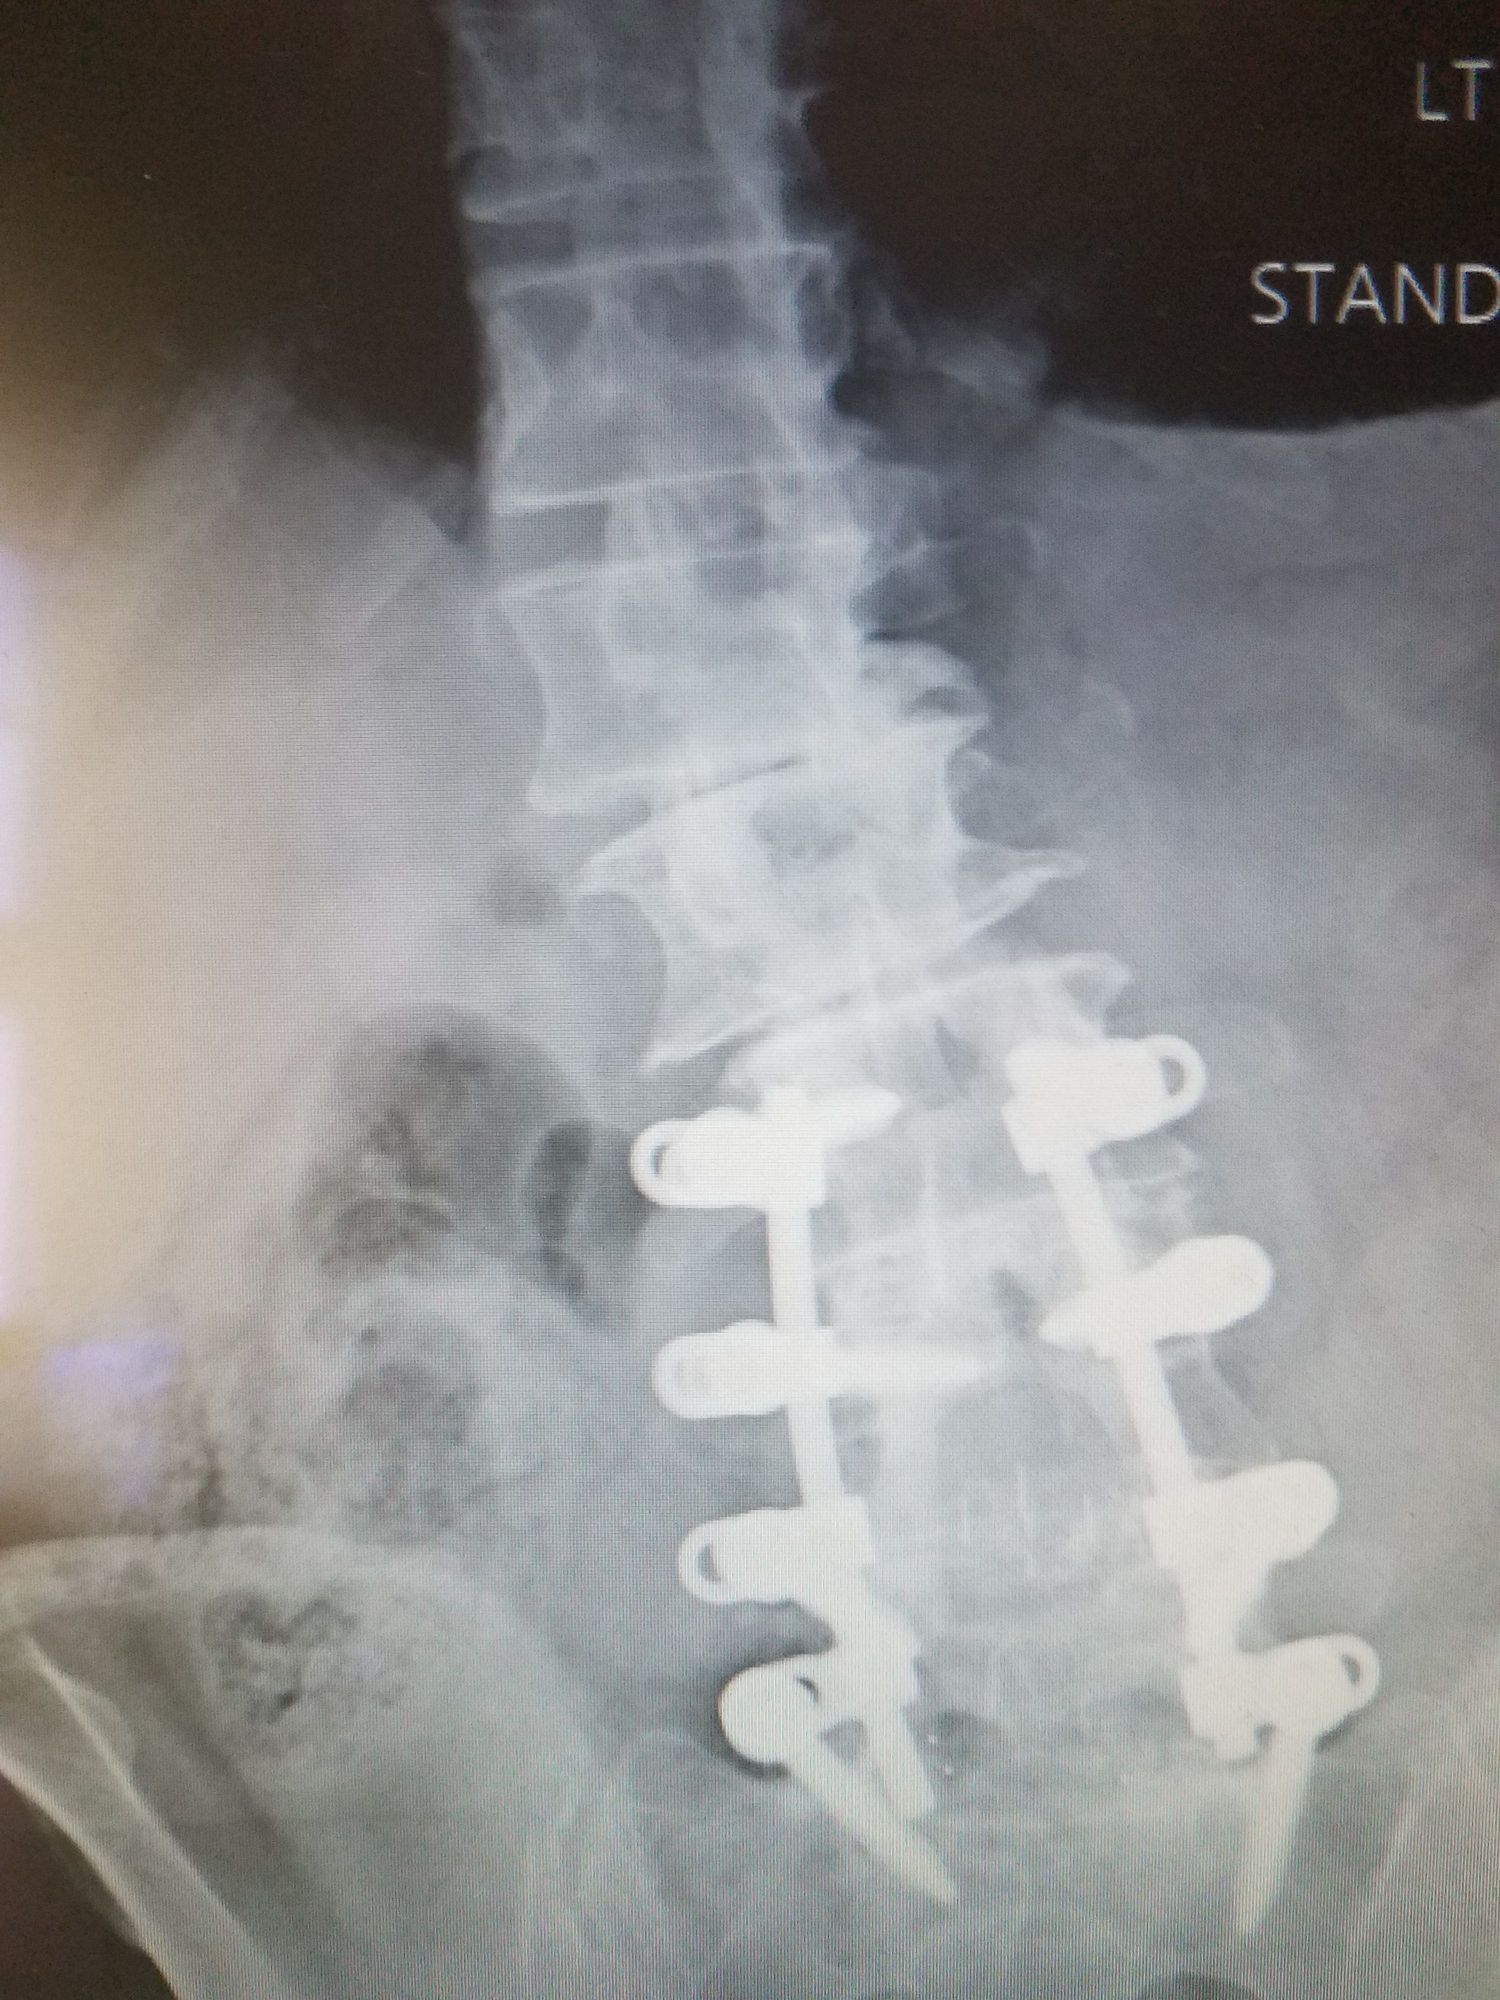

I am only 64 but as you can see my back is pretty much trashed from picking up really big lazy people and carrying them up and down stairs for the last 30+ years. I was self conscious about riding an "old man bike" until I realized that the wife and I both like being very comfortable on the Tri-Glide and more importantly I am still able to ride. I don't give a rat's ass about what anyone else thinks about me riding an old man bike anymore, neither should you. If you are still able to ride enjoy!